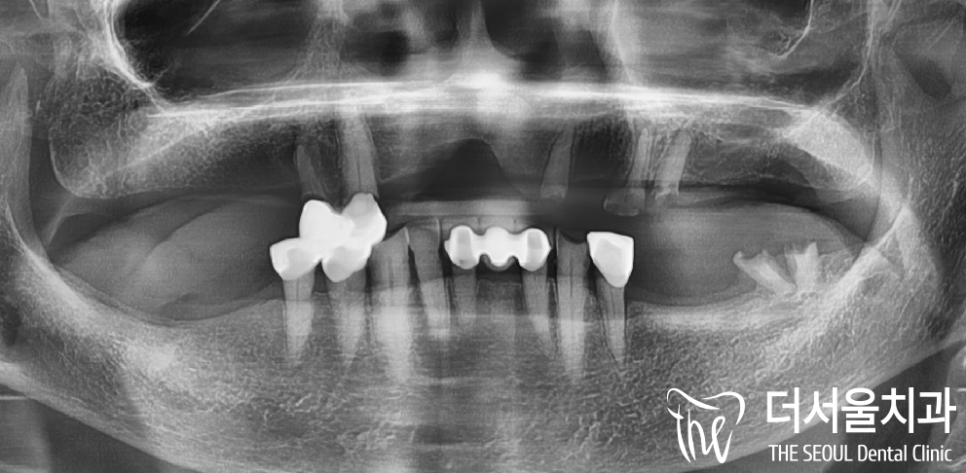

더서울치과에 오셨던 이 분의 경우,

구강 내 온전한 치아가 거의

없는 상태로 오셨었습니다.

이미, 치아의 결손 범위가 넓으셨으며

남아있는 치아들도 치근만

남아있는 곳이 거의 대다수입니다.

과거 부분 틀니를 오래 써오셨으며,

유지력을 얻게 도와줬던 surveyed crown 이

있던 위치는 치근만 남아있네요.